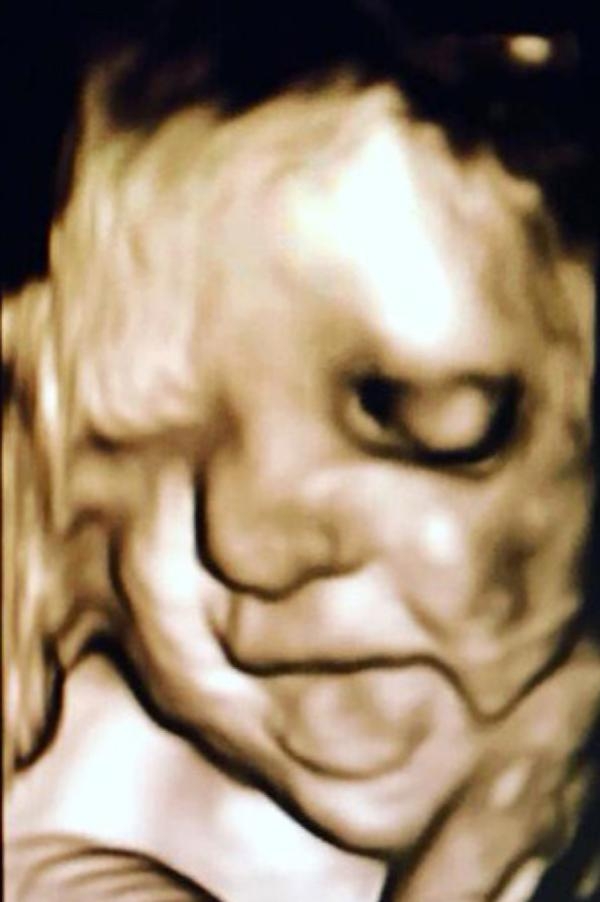

Anne adayları için en heyecanlı an olan bebeğin anne karnında ilk görüntüleri, görenlere 'Adeta poz vermiş' dedirtiyor. 16'ncı haftadan itibaren yüzü şekillenmeye ve gelişmeye başlayan bebeklerin ultrasonla çekilen fotoğrafları arasında kaşları çatık, gülen, eliyle yüzünü kapatan, burnuyla oynayan, parmağını emen, elini çenesine dayayan bebekler olduğu gibi kendini göstermeyen bebekler de var.